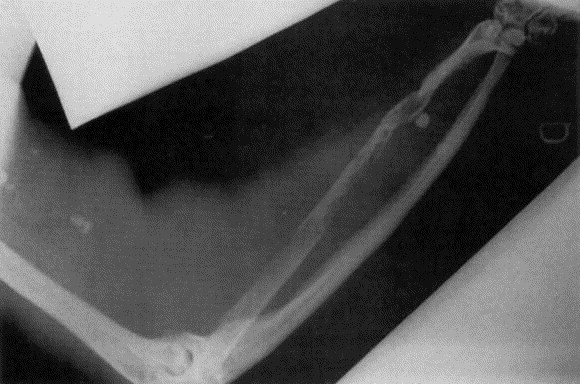

Acest termen desemnează pierderea de către schelet a elementelor minerale esențiale pentru corp, cum ar fi fosforul, calciul, sodiul, fierul, siliciul, magneziul etc.

Demineralizarea poate conduce la anemie și se manifestă prin oboseală, deficiențe la nivelul oaselor și lipsa somnului.